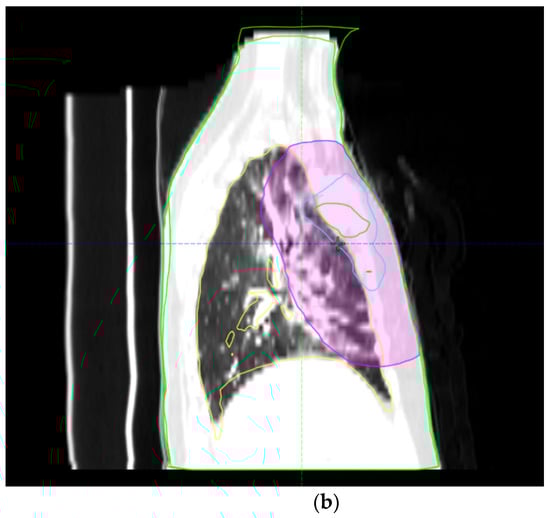

Figure 2.

(a,b) Axial and sagittal views of a chest CT scan illustrating severe radiation pneumonitis. The images feature a fusion of radiotherapy isodose lines with the CT scan, highlighting areas where pneumonitis patches coincide with the isodose lines. The purple line represents the 20 Gy isodose line, and the sky-blue line represents the 42 Gy isodose line, indicating the direct impact of radiation dose distribution on lung tissue.